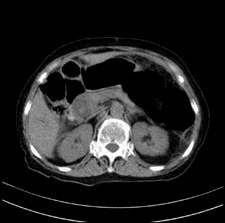

患者,女,75岁。腹痛,体黄5日,膝胸位时腹痛缓解。肝功能明日出来。彩超提示胆总管占位,未见血流信号。心电图提示s-t段改变。患者体质较弱,未能增强。

胆总管多发结石伴肝内外胆管轻度扩张。

胆总管上段,腔内有软组织密度影 ,ct值36-44hu。大家看有没有胆管癌的可能。

2楼所说胰腺内钙化不像,象脾脏血管的钙化

典型胆总管多发结石;增强扫描前后ct值是否发生改变是鉴别结石与占位的依据。

胆管没有鼠尾征,还是考虑结石